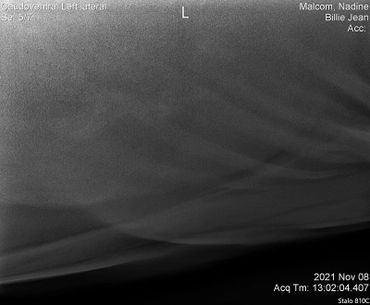

BJ had her big vet exam on November 9,2021.

We did a full wellness and lameness exam and everything looked pretty good. She showed some soreness in her right front fetlock so we did some x-rays but nothing really to see that would raise concern. We also did x-rays on her stomach and it showed she has some sand which we have been treating with Sand Clear.We didn't do x-rays on her knees. Dr. Johnson said she's probably got some fluid in there because it looks like she used to hit her knees on something a lot so we are rubbing some DMSO on it to relieve some of the swelling.Billie Jean also got a dental float. After examining her teeth closer it turns out she is more like 18-20 years old.